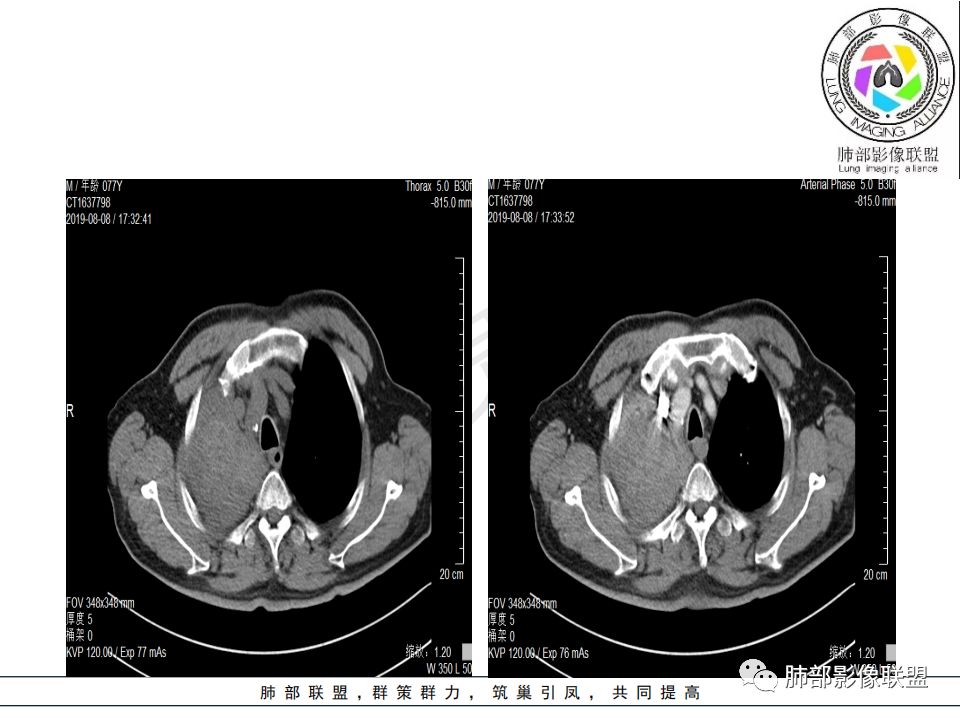

影像:影像右侧大支气管阻塞,临床没有症状或很轻微,要想到胃腺癌转移;胸壁代偿好,透亮度稍低不明显,慢性过程;34.8-52.5HU,主病灶支气管前壁另有1结节,都做成增强两期了,动脉期较平扫有强化;

晨读:患者老年男性,以咳嗽一月就诊,少量白痰,胸CT:纵隔右移,右肺体积缩小,气管下段管壁可见结节样改变,气管软骨变形,气管下段及右主支气管可见新生物向管壁浸润,并向管腔外生长,右上肺肺不张,但不张边缘可见病灶呈膨胀性生长,可见分叶,增强后强化明显。考虑:肺部恶性病变(鳞癌?)

晨读病例:老年男性,症状轻,右侧胸廓略塌陷,右肺主支气管内外软组织影,支气管变窄截断,右肺上叶不张,其内见细砂样钙化,周围看见小结节,右肺门看见一淋巴结稍大,增强不均匀强化,胃癌病史,常规考虑:转移,或原发肺恶性鳞癌。鉴别支气管TB?

降主动脉内也有啊

降主动脉的是噪声。病变内我总看着有小斑片的略高密度